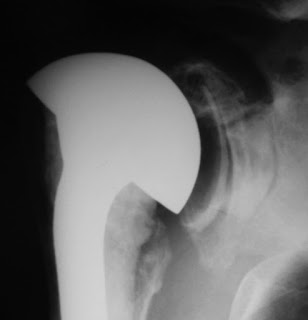

Rocking horse loosening in a superiorly unstable total shoulder

Recently we found this interesting Grashey view that nicely demonstrates superior rocking horse glenoid component loosening associated with superior instability after a total shoulder.

While no clinical information was available, the image is interesting in that it demonstrates the possible consequence when the humeral head is not centered in the prosthetic glenoid. This film also shows a substantial amount of backside cement, which we've found to predispose to glenoid component loosening.